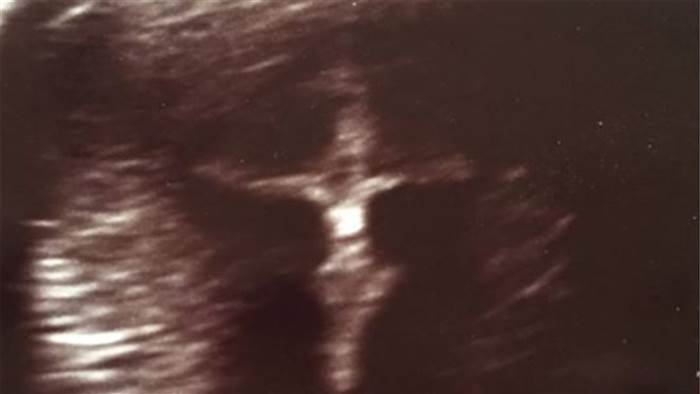

一位即將當媽媽的年輕少婦,罹患上一種發炎性腸道疾病克隆氏症,得服用藥物治療,在一次不尋常出血後,愛莉去照了超音波檢查,不料她發現照片中有

十字架上的

耶穌,頓時驚呆了,但她認為是上帝在庇佑她的孩子。

21歲的愛莉和她的未婚夫即將在六月迎接他們第一個寶寶,但因為愛莉患有克隆氏症,在一次不尋常出血後,愛莉擔心會影響胎兒去照了超音波檢查,後來經過好友提醒,才發現超音波的照片裡出現十字架和耶穌圖樣,愛莉愣住了!盯著照片看了半小時,她未婚夫覺得「恐怖」,但愛莉卻認為這是「神聖的介入」。